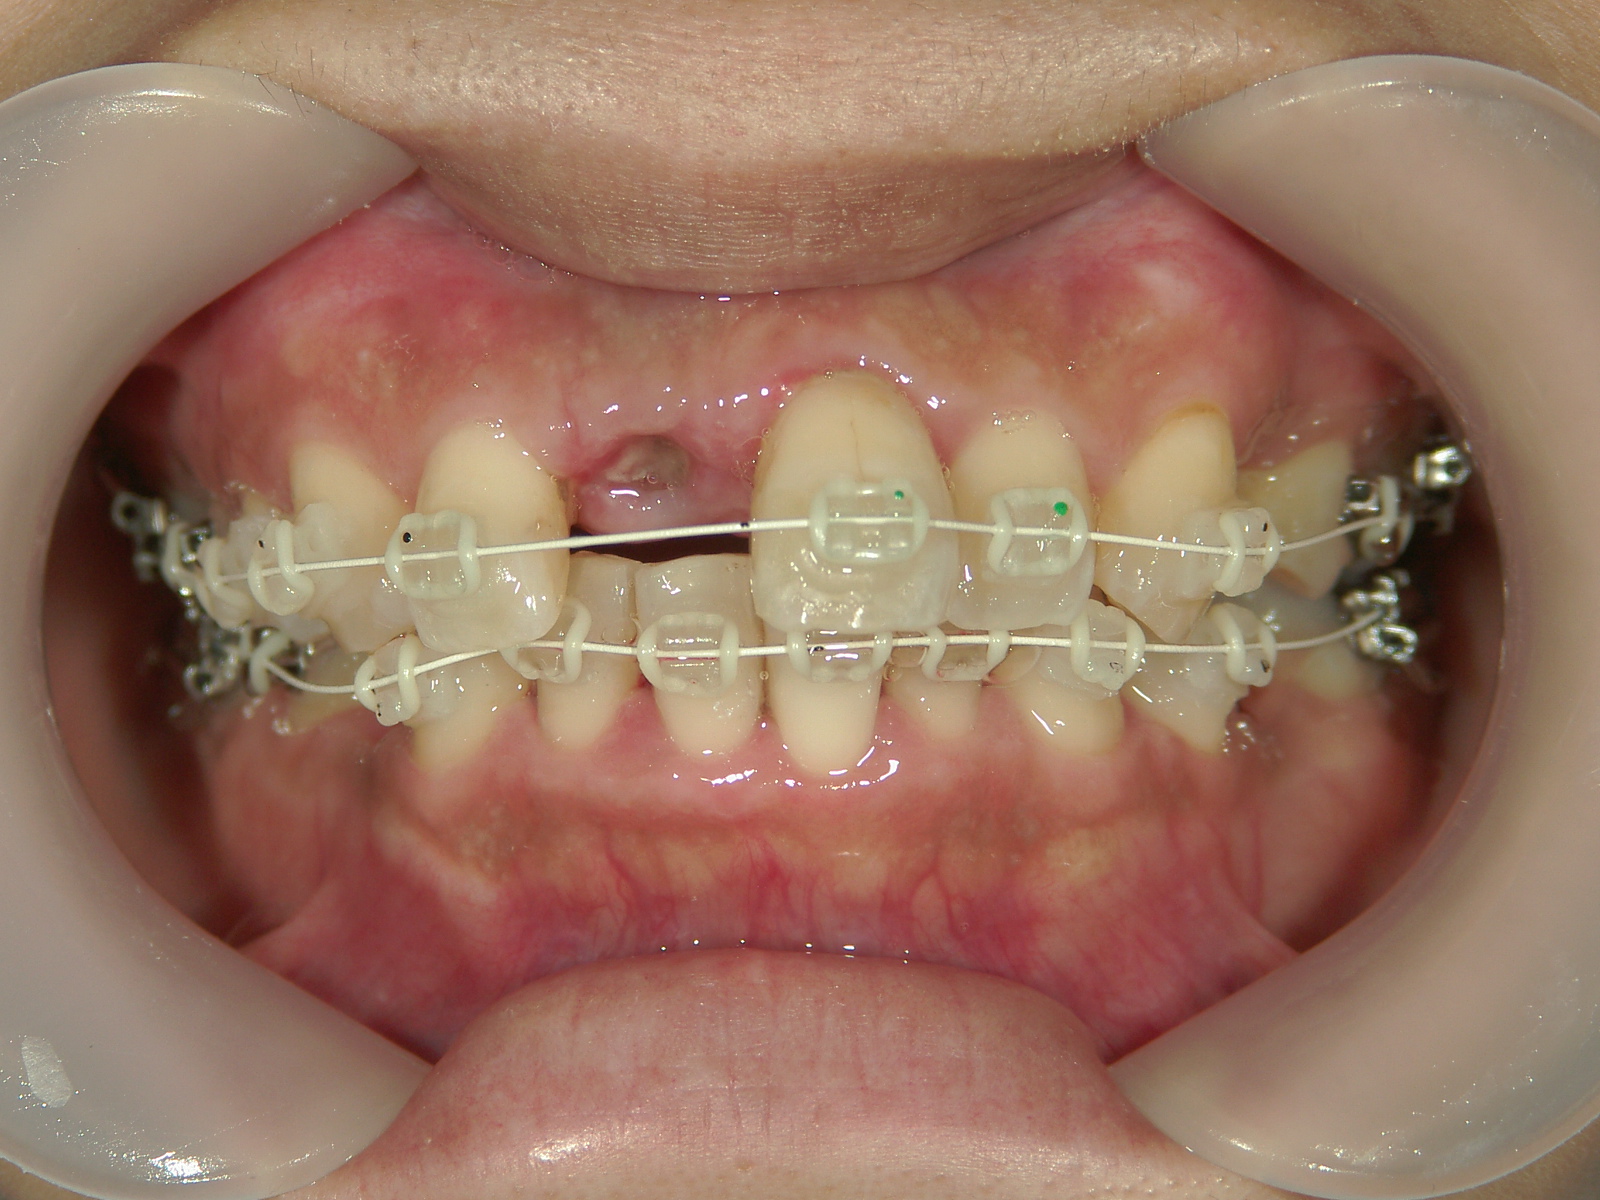

右上中切歯 抜歯後、空隙を閉鎖しました。

歯根の移動後、元々の中切歯の形に硬質レジンで歯冠を形態修正しました。

終了後に歯肉を形態修正しました。